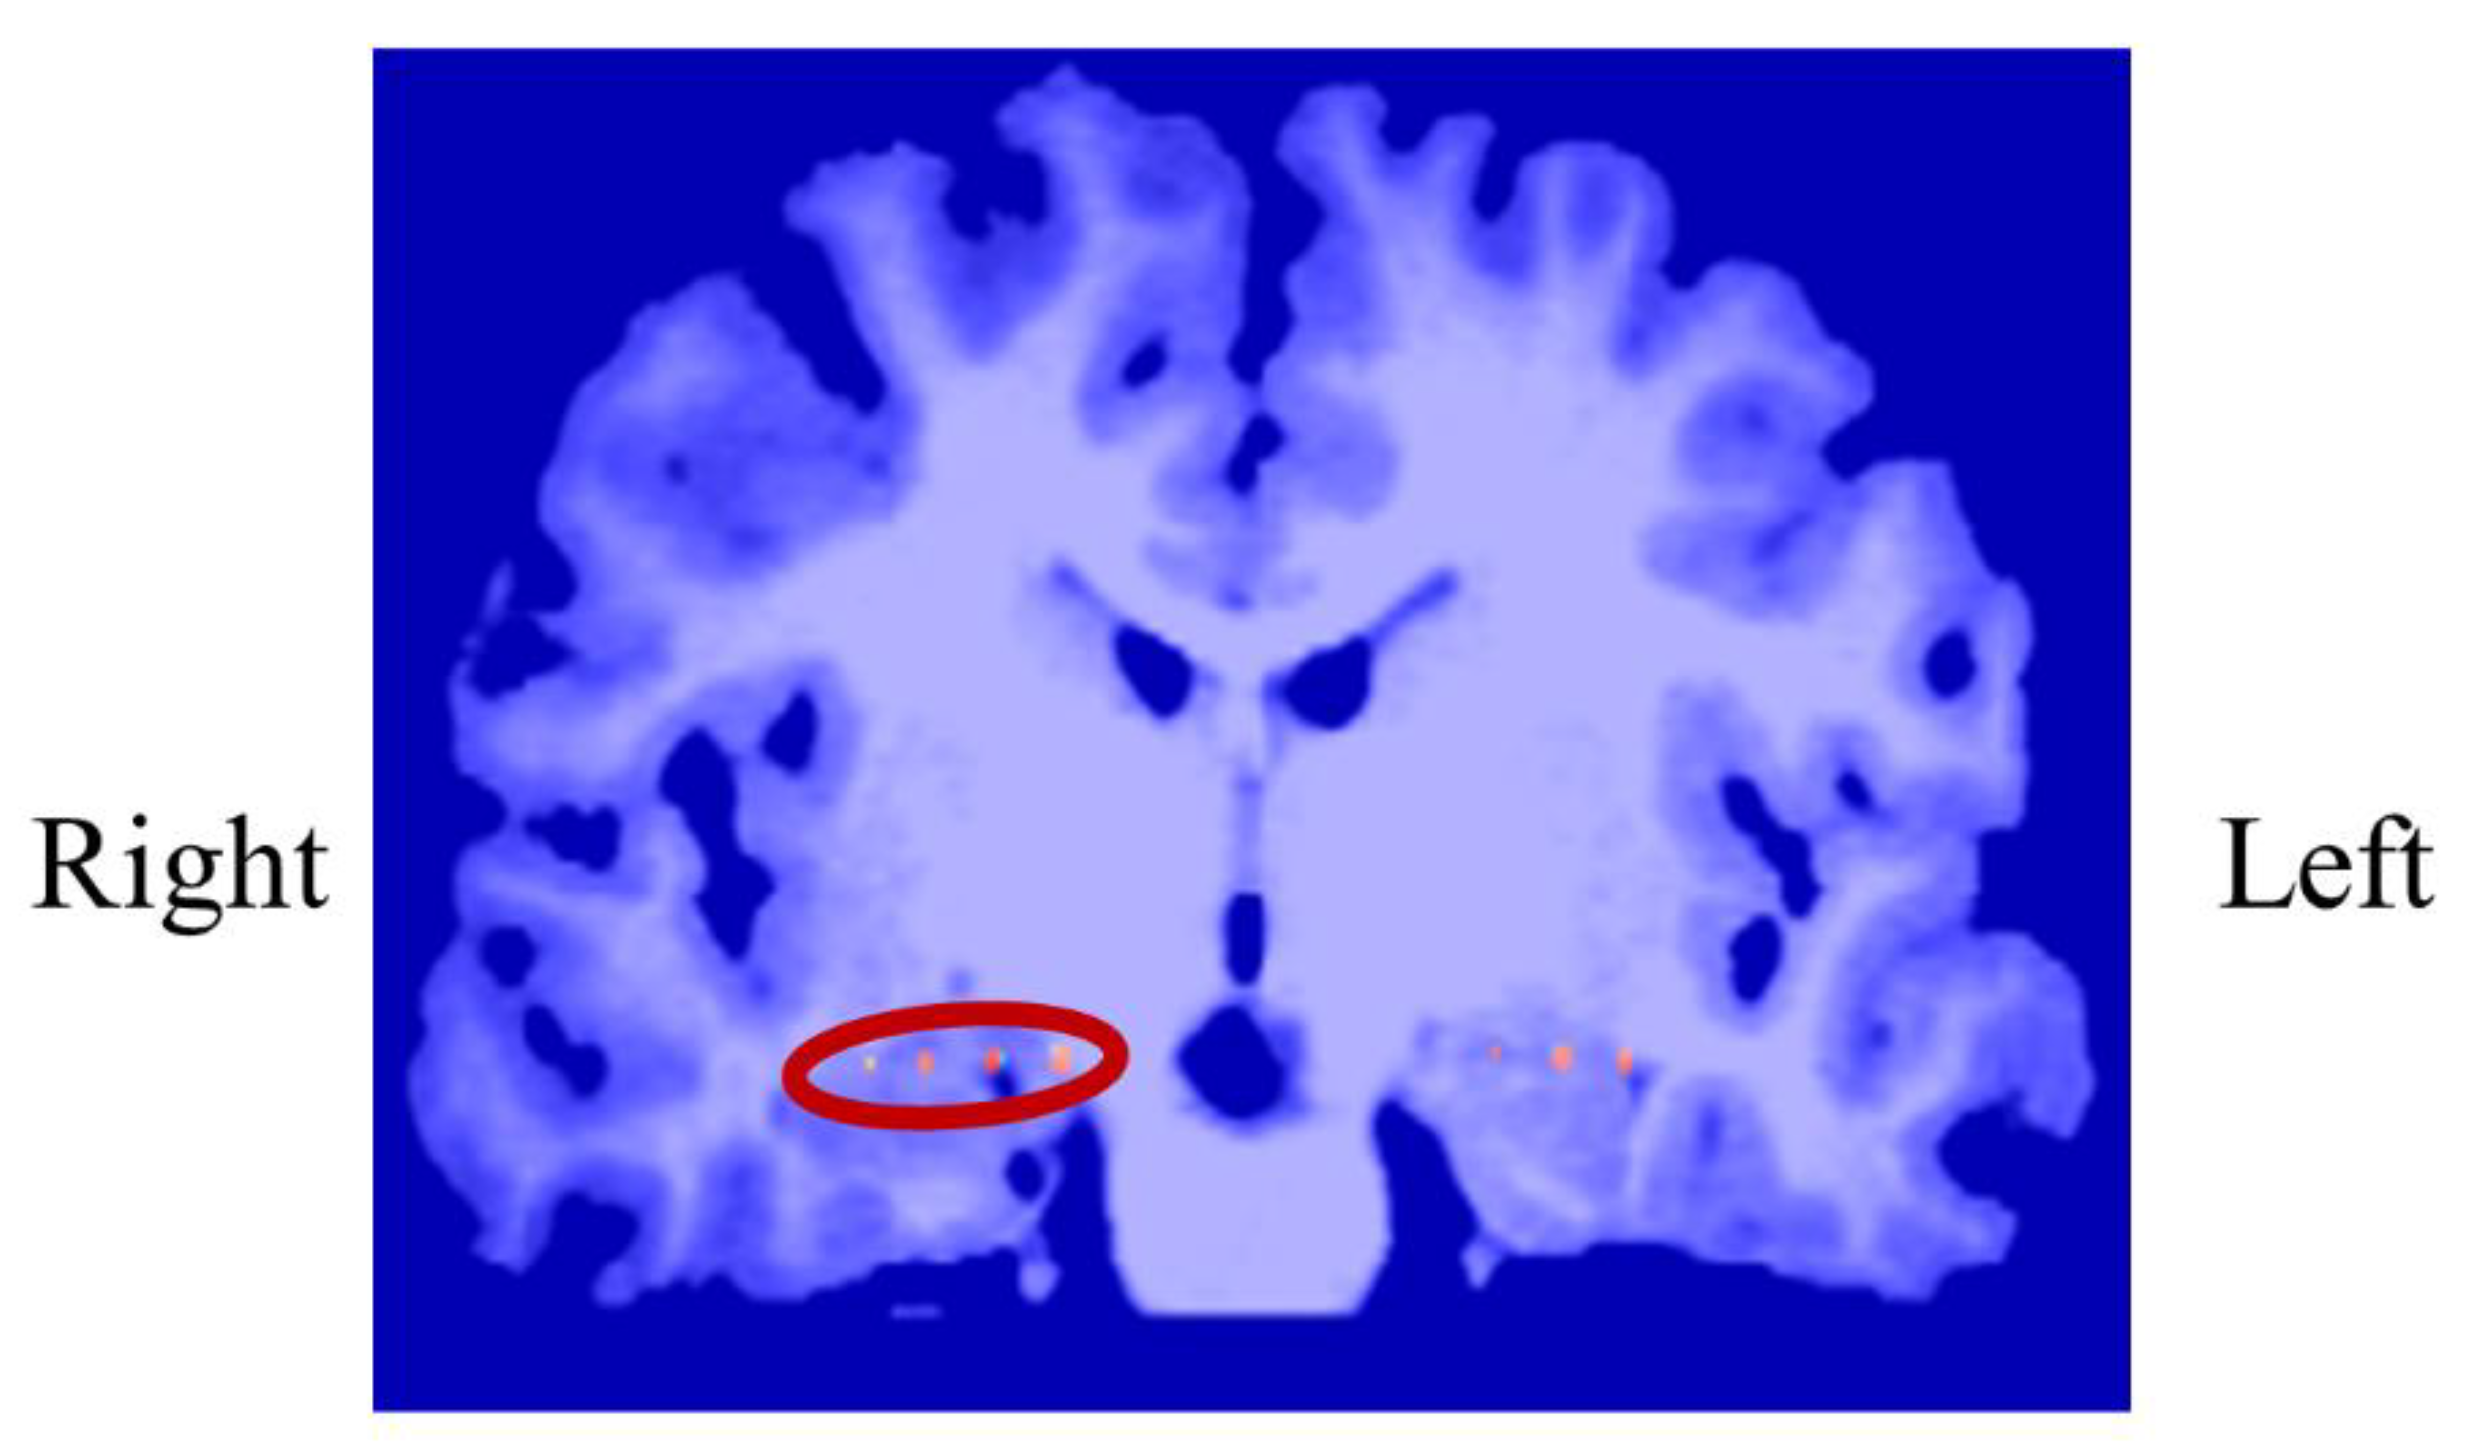

3.1.1. Intracranial Electrodes Used for Memory NF (P01)

3.3.1. Intracranial Electrodes Used for Memory NF (P03)